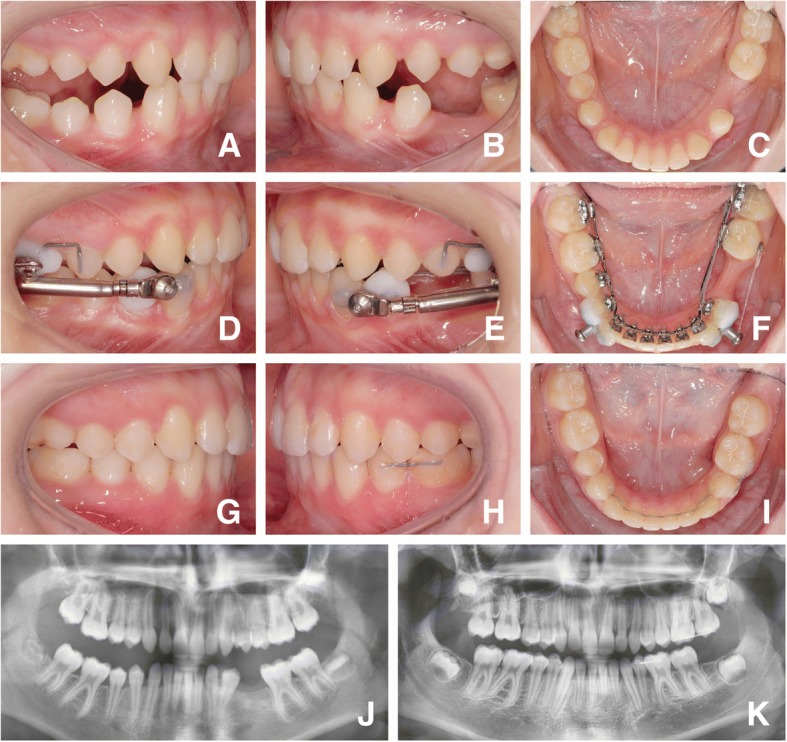

Fig. 1.

Presentation of a case: Initial situation prior to bonding of the fixed lingual appliance at T0 (a, b, c); Figs. A and B were taken following pre-treatment with removable functional appliances, hence the mandible is seen in a protruded sagittal position. Following leveling and aligning and initiation of anchorage reinforcement by adding Herbst telescopes at T2 (d, e, f), and at T3 following de-bonding of the fixed lingual appliance. Posterior maxillary 6–7 retainers aid in maintaining the vertical relation until lower third molars are brought into occlusal contact, while mandibular 4–6 retainers prevent re-opening of aplasia spaces (g, h, i). Panoramic x-rays show an adequate root parallelism after completion of aplasia space closure (j, k)